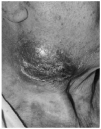

En seis de 50 pacientes con MF/SS (12%) se desarrolló transformación a LCG (tabla I). Todos ellos eran varones y la edad media fue de 61 años (intervalo: 49-77). La localización inicial del LCG fue en la piel en cuatro casos, en los que se manifestó de forma de tumores cutáneos de crecimiento rápido, excrecentes, infiltrados en base, de coloración violácea y superficie lisa o erosiva con escamocostra superficial (Figs. 1 y 2). Los dos casos restantes se presentaron con clínica extracutánea, uno en forma de adenopatías axilares y otro con un cuadro de dolor abdominal por invasión de la pared gástrica.

FIG. 1.--Tumor localizado en cuello, violáceo, excrecente, infiltrado, con escamocostra superficial.